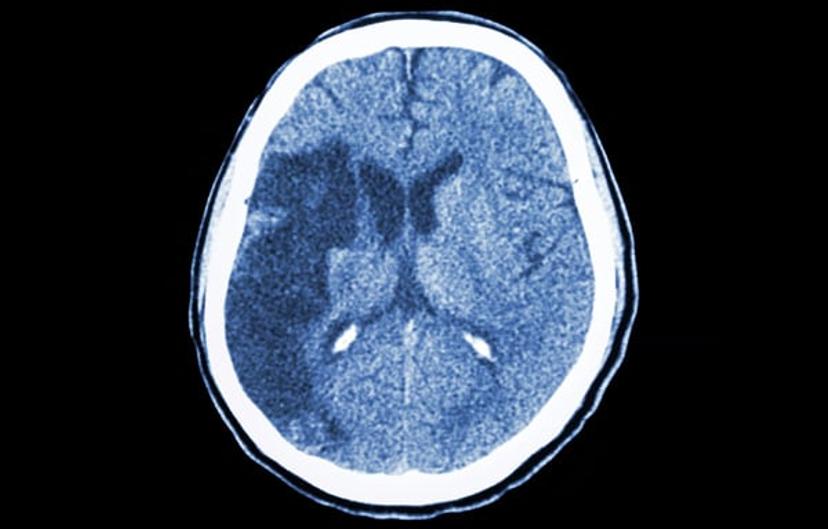

Ischemic stroke is caused when blood supply to the brain is cut off, most often as a consequence of atherosclerosis with the formation of blood clots. Rapid treatment is necessary to prevent damage to the brain through restoration of oxygen supply. Factors in damage caused by ischemic stroke, including exitotoxicity and oxidative stress, have been identified as potential targets for new theraputics.